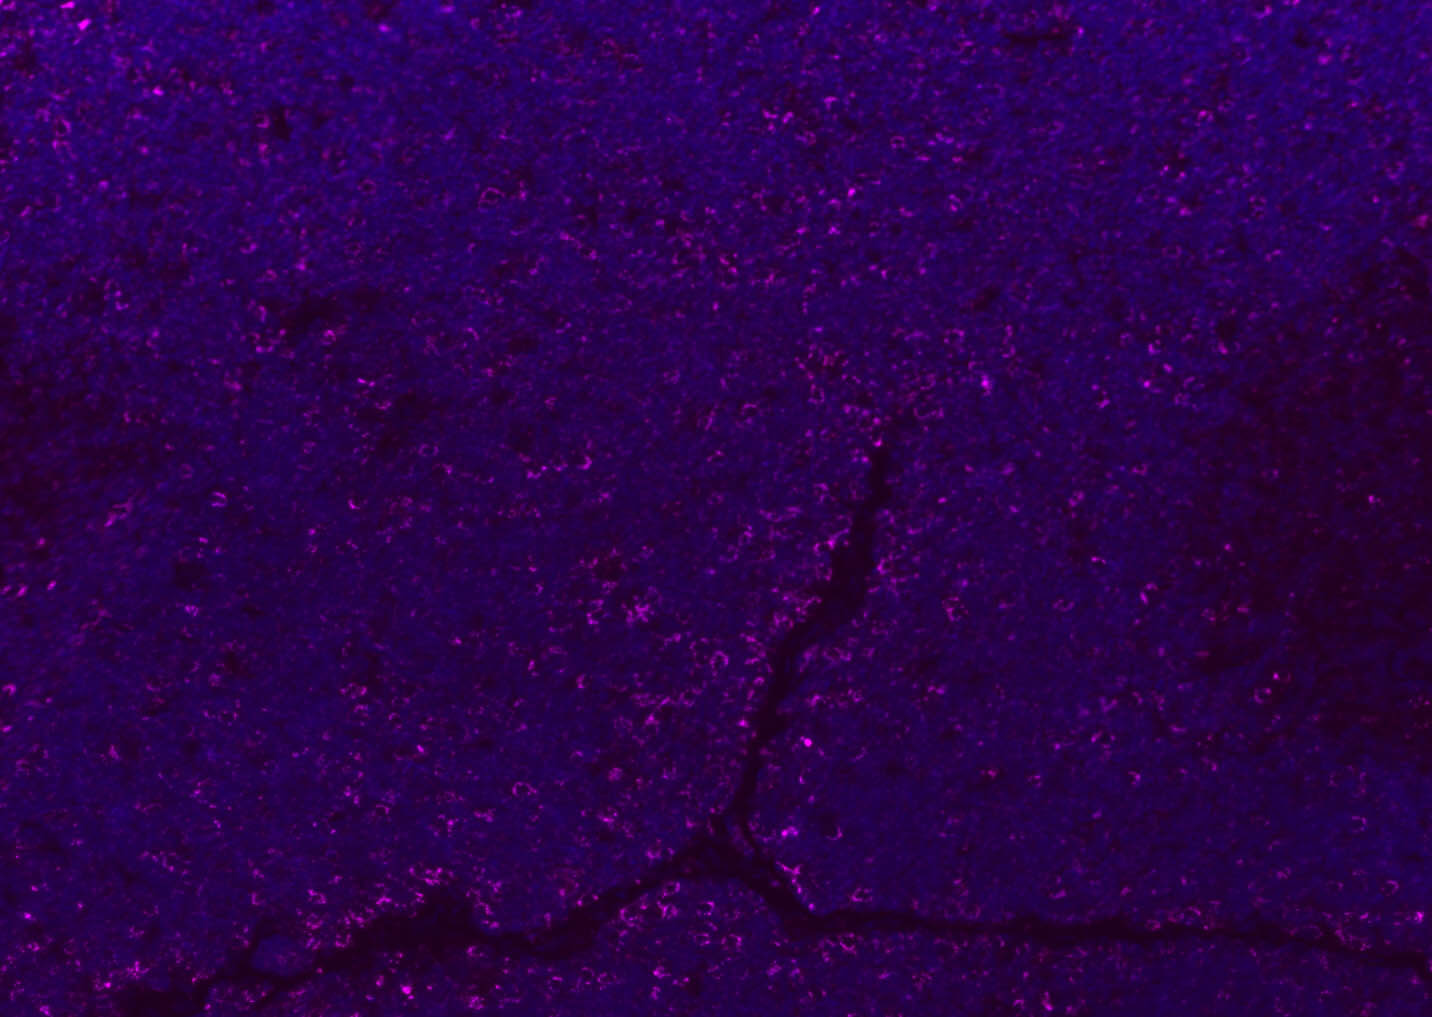

Tissue/cell: human lung carcinoma;4% Paraformaldehyde-fixed and paraffin-embedded; Antigen retrieval: citrate buffer ( 0.01M, pH 6.0 ), Boiling bathing for 15min; Blocking buffer (normal goat serum,C-0005) at 37℃ for 20 min; Incubation: Anti-CD8 Polyclonal Antibody, Unconjugated(bs-4914R) 1:200, overnight at 4°C; The secondary antibody was Goat Anti-Rabbit IgG, Cy3 conjugated(bs-0295G-Cy3)used at 1:200 dilution for 40 minutes at 37°C. DAPI(5ug/ml,blue,C-0033) was used to stain the cell nuclei